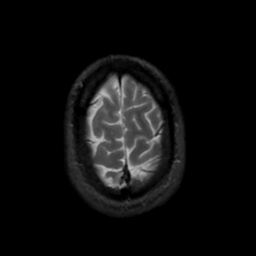

MR Study #7, March 24, 1991 -- Slice #44

[Home][Help][Clinical][Tour 1][Tour 2] Slice 44